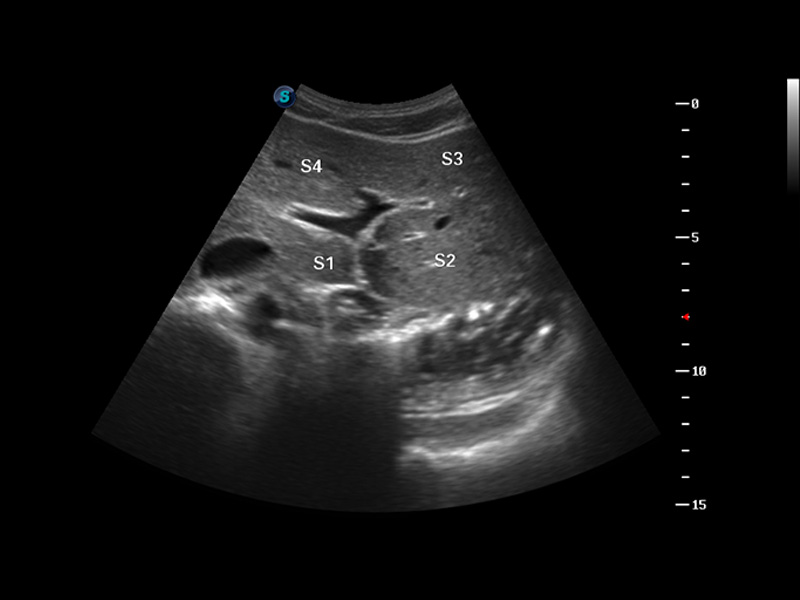

S8 EXP便携式彩色多普勒超声诊断仪是百老汇电子游戏官网研发的高端全身应用型便携彩超。高通道的VIS平台融合可视化(Visual)、智能化(Intelligent)和人性化(Smart)的特点,配以百老汇电子游戏官网自主研发生产的探头大家族,使您能够快速、准确的获得病人信息,提高工作效率的同时减轻疲劳。

成像技术

μ-Scan微米成像

谐波成像